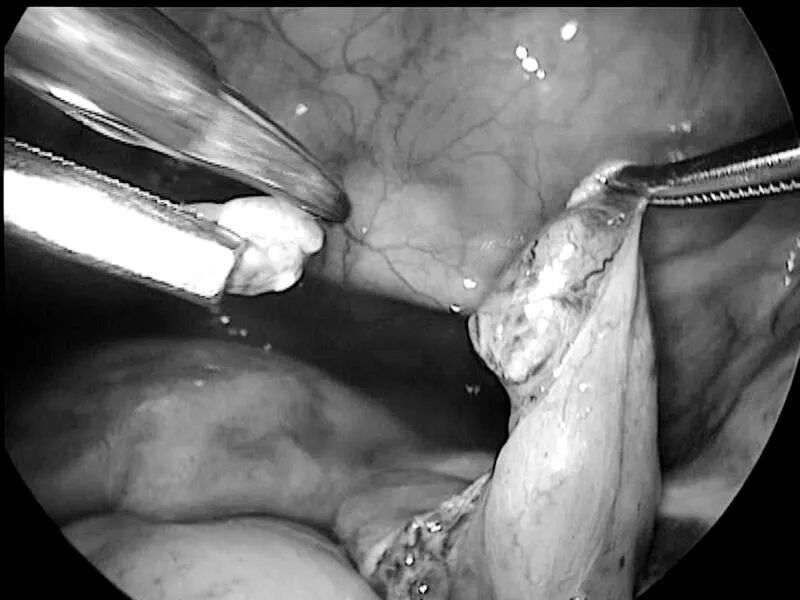

“这个手术主要是在腹腔镜下将原来结扎的输卵管切开,并剪除以前结扎的伤疤,再重新将两侧断开的输卵管用线缝合好。”在周留林的口中,这个说起来简单的手术,但做起来却并不容易。

输卵管是连接在子宫两侧的管状结构,长度在8—14cm之间。管腔直径最大处也不超过1cm,最窄处在0.9—2mm,将如此细微的输卵管缝合难度可见一斑。“缝合时需要特别注意对合要良好,稍有偏差就会使输卵管扭曲或者会影响其管腔的通畅度,这样都会影响术后患者的怀孕成功率。这考验手术医生的技术和经验,是目前较难的妇科手术之一。”

当天,经过近两小时的精细操作,周留林团队为其实施了腹腔镜下输卵管再通手术。手术最后,当腹腔镜下见到双侧输卵管均顺畅地流出了输卵管通液后,手术室内的同事都纷纷喝彩。